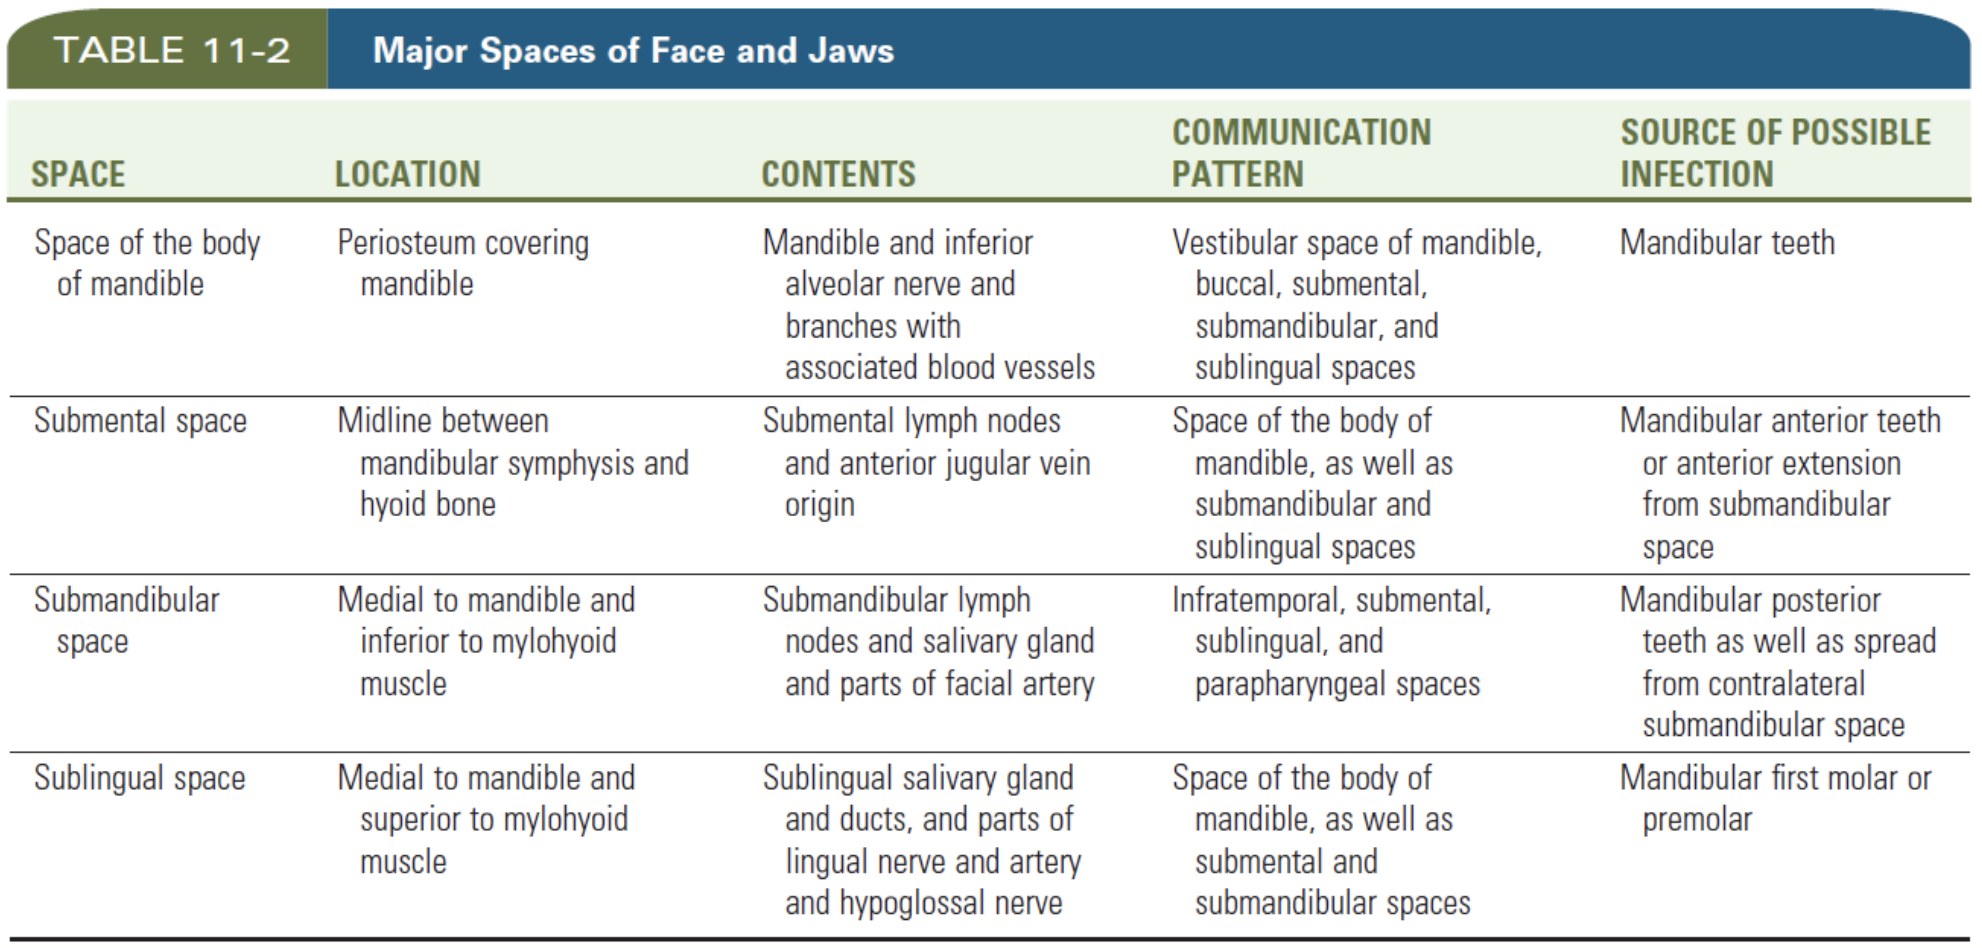

Space

Vestibular space

- of Maxilla

- of Mandible

Submental & Submandibular space

Submental

- Digastric, Hyoid bone, Mandibular symphysis 為界

- Superficial cervical fascia為底,Mylohyoid m. 為頂

Sublingual space

- Lingual n./a.

- Hypoglossal n.